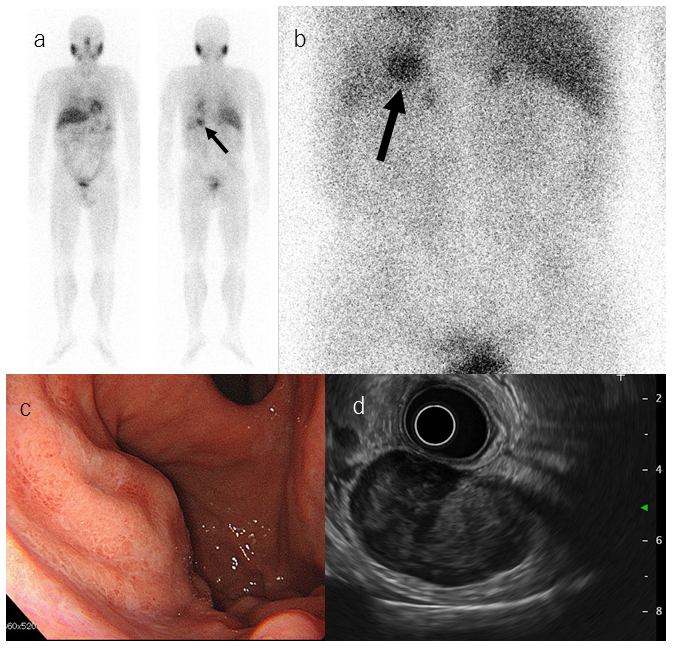

Meta-iodobenzylguanidine (MIBG) is an analog of norepinephrine and guanethidine, and MIBG scintigraphy is useful to diagnose tumors of the sympathetic nervous system, such as pheochromocytoma, paraganglioma, and neuroblastoma. To date, there have been few reports of MIBG accumulation in gastrointestinal stromal tumors (GISTs), so the mechanism and frequency of MIBG accumulation in GISTs are unknown. Herein, we report and discuss three cases of GIST in which scintigraphy that was performed to exclude pheochromocytoma showed MIBG accumulation.